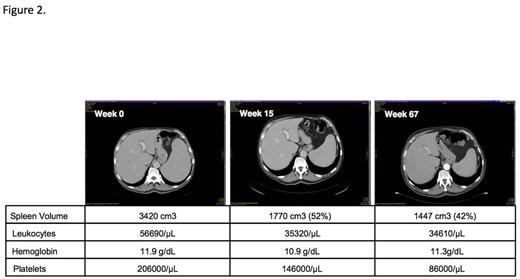

Results:Up to now targeted NGS data are available in 116 patients and in vitro culture data in 75 patients respectively. We identified 13 CMML patients who had a JAK2 V617F mutation with an allele frequency >10%. Clinical, hematological, and biologic characteristics in these patients were compared with 103 patients who had NGS sequencing and were negative for the JAK2 V617F mutation. As shown in Table 1 JAK2 V617F-positive CMML patients had significantly higher WBC counts, higher hemoglobin values, higher platelet counts and more pronounced splenomegaly as compared to JAK2 V617F-negative patients. On the other hand the percentage on monocytes in peripheral blood and the numbers of CFU-GM growing in vitro without addition of exogenous growth factors were lower in CMML patients with the JAK2 V617F mutation as compared to patients without this mutation. The majority of JAK2 V617F-positive patients had additional mutations that can be also found in JAK2 V617F-negative patients, in particular mutations in genes of epigenetic regulation and RNA-splicing, respectively. As shown in Figure 1 there was a trend towards a better survival of patients with the JAK2 V617F mutation as compared to JAK2 V617F-negative patients (p=0.05). In a JAK2 V617F-positive CMML patient with splenomegaly, who was treated with the JAK1/2 inhibitor ruxolitinib off label, we were able to demonstrate the disappearance of constitutional symptoms and a durable spleen response lasting for over 56 months (Fig. 2).